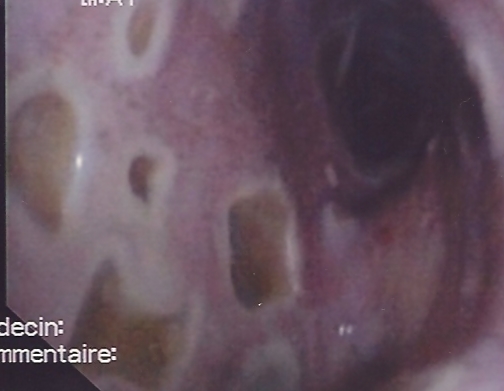

Multiple mucosal ulcers

Co-infection by Herpes simplex virus type 1, influenza A H1N1 and aspergillus.